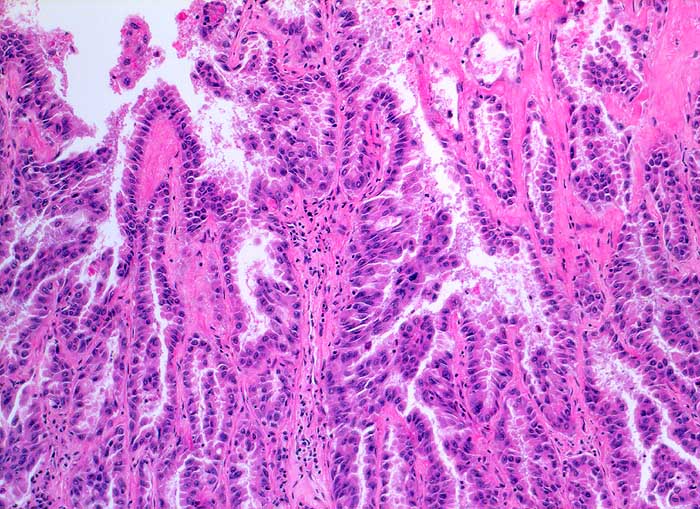

PathoPic ID 5812 - Adenokarzinom der Lunge

Adenokarzinom der Lunge

maligner Tumor

Lunge

Papilläre und tubuläre Strukturen ausgekleidet von atypischem hochprismatischem Epithel entsprechend einem hochdifferenzierten Adenokarzinom.

Histologie

100

59